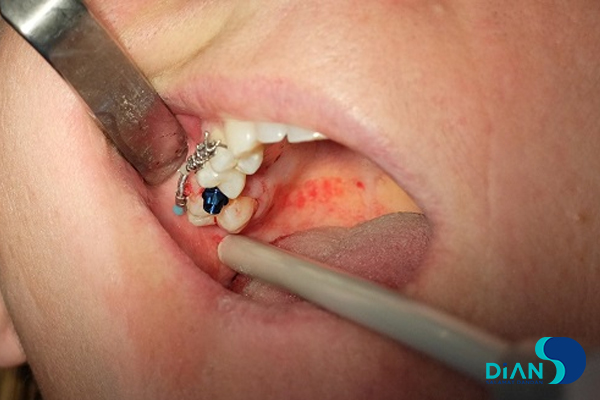

The experienced dentist Dr. Müesser Aktaş from Turkey successfully performed a dental implant procedure using Bio3 Implants in the molar region. For this operation, Dr. Aktaş utilized the Bio3 surgical kit, which is specifically designed to provide precision, ease of use, and efficiency during implant placement. The system’s user-friendly design and reliable components allowed for a smooth and accurate procedure, ensuring optimal results for both the patient and the clinician. This case once again highlights the practicality and advanced engineering of Bio3 Implants, making them a trusted choice for dental professionals worldwide.

Implantation in Molar Area